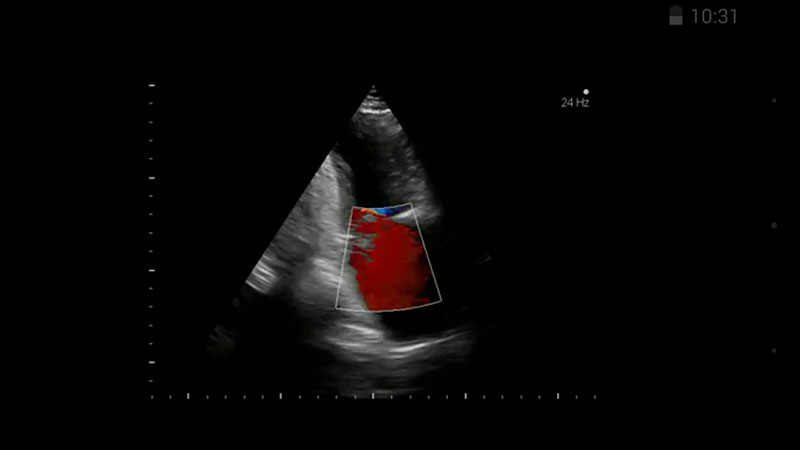

The website's and app's library contains various medical videos, surgical videos, photos of medical cases, visualizations and animations. MEDtube also contains interviews, presentations, webcasts, case-reports and other professional materials in all medical specialties, shared by physicians, medical societies and institutions, while some are produced by MEDtube. The app and the website are currently available in four language versions: English, French, German and Polish.

Once you select a category or a topic you've searched for, you'll get a list of related videos with a short description of what the video is about, number of view and a 5-star rating system. Videos range from short, lasting only couple of seconds, to longer, depending on the procedure or condition they described. We've noticed that the majority of the videos within the app seem to be surgery related. Also, during our review, we didn't notice any lecture based or animated medical videos, but we think that MEDtube app might benefit from them immensely.